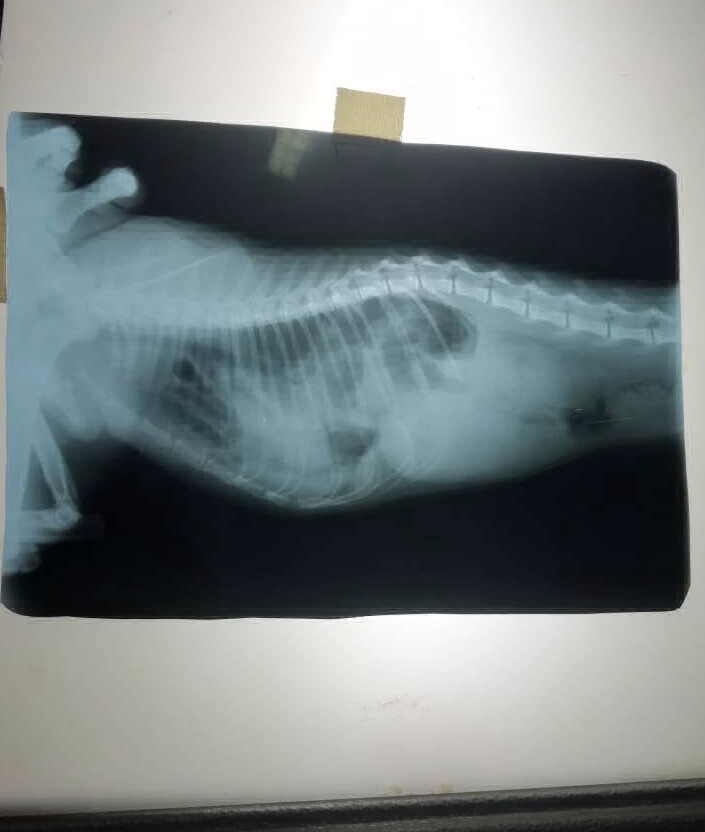

Luego de varios estudios, a Toto se le diagnosticó que tenía una hernia diafragmática, y tenía que someterse a cirugía cuanto antes para reparar el defecto.

Toto estaba en peligro, tuvimos que esperar 48 horas, que fueron fundamentales para que los veterinarios aprobaran la cirugía.

Debido a su evolución exitosa, se programó urgente una cirugía para tratar la hernia diafragmática que ponía en riesgo su vida.